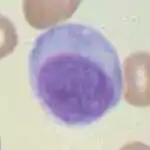

Micrograph of a plasma cell with distinct clear perinuclear region of the cytoplasm, which contains large numbers of Golgi bodies. | |

Plasma cells are large lymphocytes with abundant cytoplasm and a characteristic appearance on light microscopy. They have basophilic cytoplasm and an eccentric nucleus with heterochromatin in a characteristic cartwheel or clock face arrangement. Their cytoplasm also contains a pale zone that on electron microscopy contains an extensive Golgi apparatus and centrioles (EM picture). Abundant rough endoplasmic reticulum combined with a well-developed Golgi apparatus makes plasma cells well-suited for secreting immunoglobulins.[2] Other organelles in a plasma cell include ribosomes, lysosomes, mitochondria, and the plasma membrane.